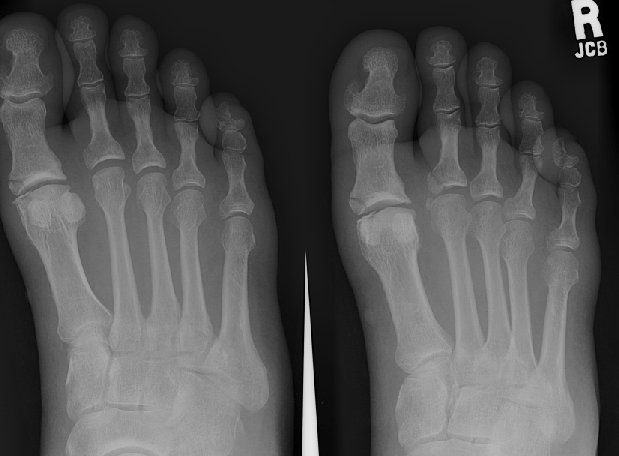

Return to Phalangeal Fracture (Foot)